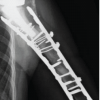

Patient pre-anesthetic evaluation workup was done and posted for surgery. The patient was placed supine on a fracture table, after standard painting and draping, and slight traction was applied. Moreover, closed reduction of the fracture was attempted and achieved under C-arm guidance. A small lateral incision was made proximal to the greater trochanter. An entry point was made at the tip of the greater trochanter under image guidance, and a guidewire was passed through the proximal femur into the shaft. Reaming was done over the guidewire sequentially. A long proximal femoral nail (PFN) (length: 28 cm, diameter: 9 mm) was inserted over the guidewire. Fracture alignment was confirmed under C-arm. 8 mm and 6 mm proximal locking screws were inserted through the jig. Distal locking was done using the freehand technique under C-Arm. Final fluoroscopy confirmed satisfactory fracture reduction, implant position, and screw placement. The wound was irrigated with saline, and hemostasis was ensured. Wound closure was done in layers. A sterile dressing was applied. The post-operative patient was allowed toe-touch with a Zimmer walking frame. Clinical and radiographic follow-up showed no displacement and consolidation after 8 weeks, and hence, full weight-bearing was started as tolerated. The patient was followed up after 5 months, and her physical status was almost comparable to the pre-operative level without any complications (Fig. 3, 4, 5, 6).

Figure 3: Immediate post-operative X-rays.

Figure 4: Partial-weight bearing X-rays after 2 weeks.